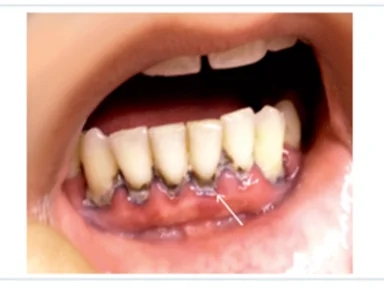

앞니 크라운 후 잇몸이 까맣게? 교체가 필요할 수도 있습니다.

앞니 치료 후 까만 잇몸, 그냥 두면 안 되는 이유 앞니 크라운이란? 심미성과 기능을 모두 고려한 보철 치...